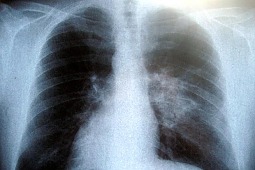

Zatorowość płucna jest schorzeniem częstym i niesie ze sobą wysokie ryzyko wczesnego zgonu.

Obecnie, chorych z rozpoznanym zatorem tętnicy płucnej wysokiego ryzyka, coraz częściej kwalifikuje się do intensywnego leczenia farmako-mechanicznego. Jedną z alternatyw tego typu leczenia, jest zastosowanie systemu trombektomii mechanicznej Angio-Jet Ultra.